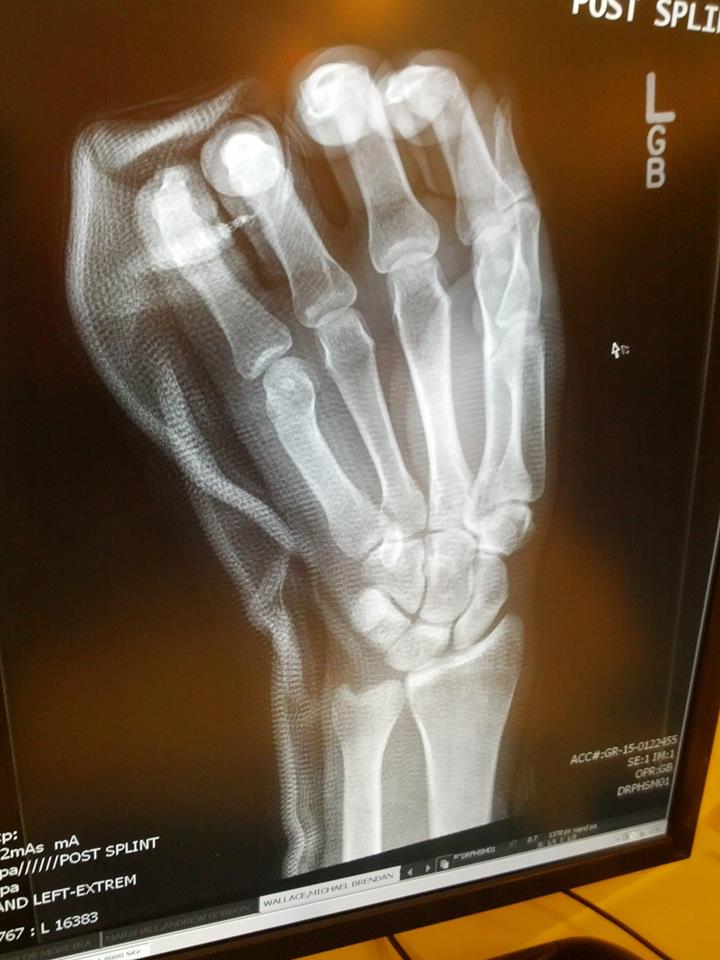

3/15, Indianapolis at Joyful Noise is where the mayhem began; perhaps it was one too many birthday shots, or the power going out right as we embarked upon the last song of our set ("Death"). A short intermission and Jurassic Park was back online, I busted my distal 5th metacarpal in the last verse on the rim of the snare drum #gnarbounty #joyfulnoise #vietcong

"XRAY"

I'm a big fan of irony most of the time, but this dose is a bit much considering the term "Boxers Fracture", and the cover our self-titled record! #boxersfracture #gnarbounty